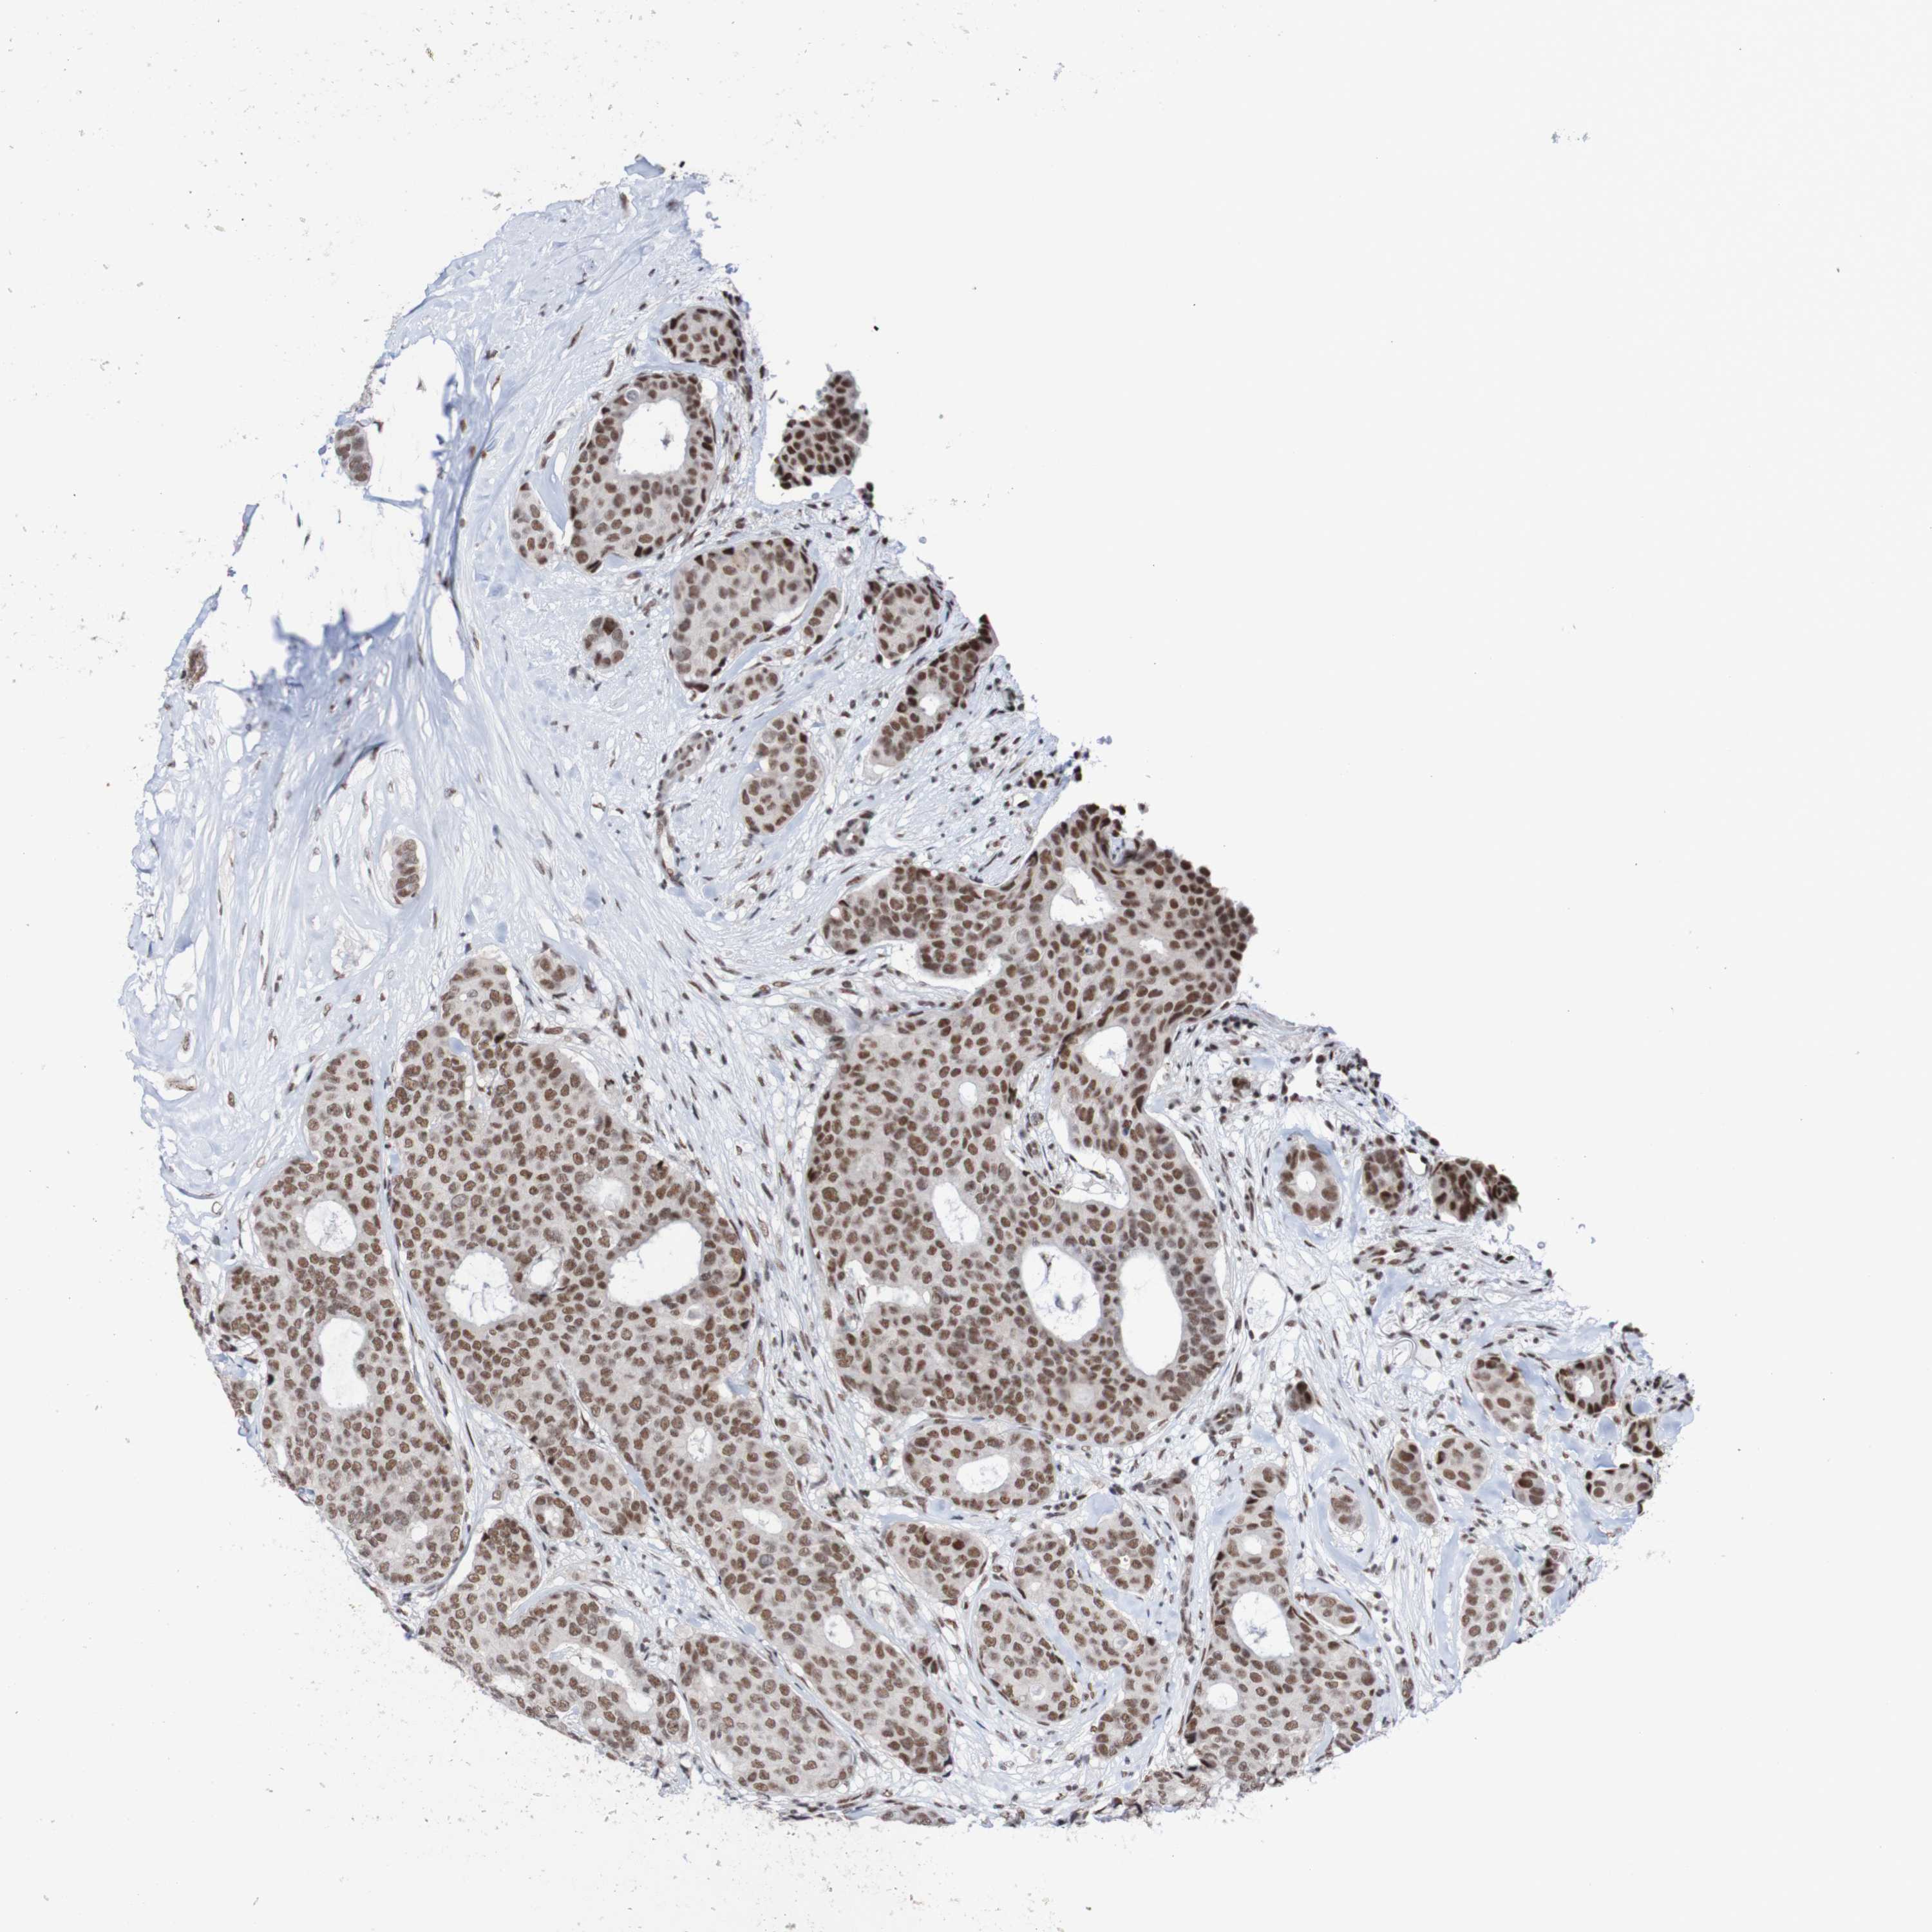

CANCER BREAST CANCER Show tissue menu

BRCA TCGA BRCA VALIDATION PROTEIN EXPRESSION